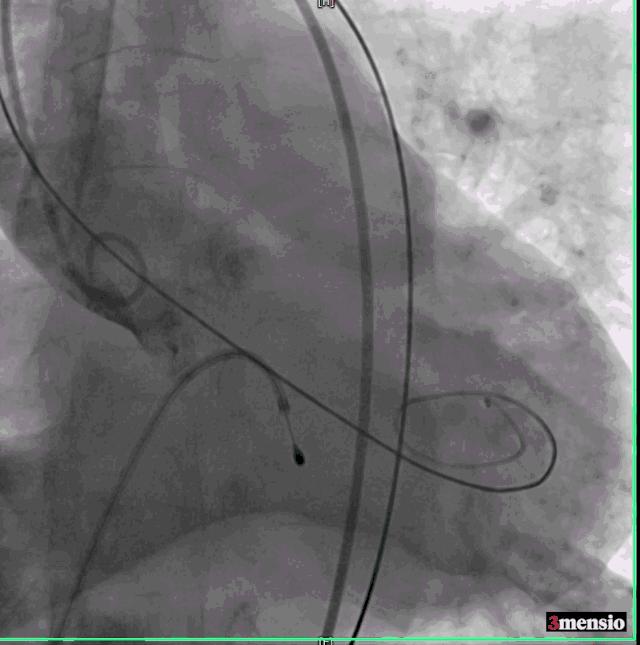

然而瓣膜释放后患者出现室颤,再次面临命悬一线的险境,术者团队处危不惊,快速予以除颤处理,患者成功恢复为窦性心律,转危为安。

复查造影示轻度主动脉瓣返流,同时行床边经食道心脏彩超,未见明显瓣周漏,瓣膜功能良好。升主动脉压力156/92mmHg,跨瓣压差<10mmHg。患者生命体征平稳,送返病房,密切监测生命体征变化。

最后造影